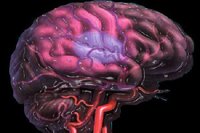

Prendre en charge l'accident vasculaire cérébral

TOP SANTE.COM: devant tout symptôme de déficit neurologique brutal, tel que perte de force ou engourdissement au niveau du visage ou d'un membre, difficultés d'élocution, le premier réflexe doit être d'appeler le 15, le numéro du SAMU. Le but est le transfert rapide du patient vers un établissement hospitalier et au mieux d'emblée vers une unité neuro-vasculaire. Cette prise en charge en urgence permet la confirmation de l'AVC grâce à l'imagerie (IRM si possible sinon scanner) et la réalisation dune thrombolyse en cas d'infarctus cérébral confirmé et en l'absence de contre-indication.

TOP SANTE.COM: devant tout symptôme de déficit neurologique brutal, tel que perte de force ou engourdissement au niveau du visage ou d'un membre, difficultés d'élocution, le premier réflexe doit être d'appeler le 15, le numéro du SAMU. Le but est le transfert rapide du patient vers un établissement hospitalier et au mieux d'emblée vers une unité neuro-vasculaire. Cette prise en charge en urgence permet la confirmation de l'AVC grâce à l'imagerie (IRM si possible sinon scanner) et la réalisation dune thrombolyse en cas d'infarctus cérébral confirmé et en l'absence de contre-indication.